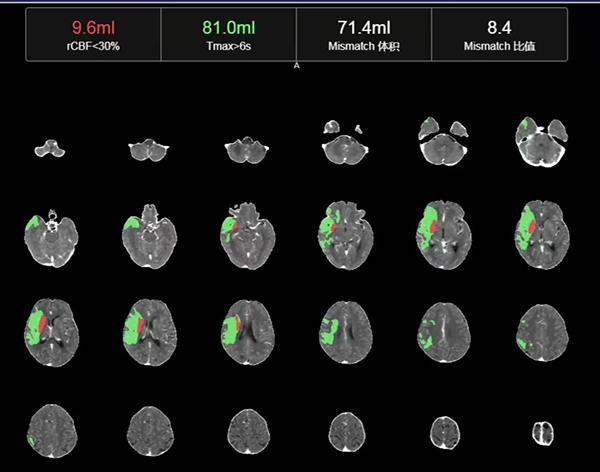

两难之间,急需进一步明确手术指征,王建峰主任决定采用进一步的高阶影像学检查——颅内CT灌注成像(CTP)指导手术治疗。CT灌注成像(CTP)是一种广泛使用于急性脑卒中的高级成像技术,对于超时间窗颅内大血管闭塞的急性脑梗死患者,近年来国内外专家均推荐术前使用CTP进行评估来筛选合适的患者进行颅内动脉取栓术,以最大限度提高手术获益,保障患者安全,减少术后高灌注出血。

CTP检查结果提示,姬阿姨颅内核心梗死体积约9.6ml(红色区域),但低灌注区域体积高达81ml(绿色区域)(图2),低灌注区域越大,代表可挽救的脑神经细胞越多,手术开通的价值越大,可见患者颅内低灌注区域远远大于核心梗死区域,颅内动脉取栓术手术指征进一步明确。在与患者家属积极沟通,征得家属同意后,王建峰主任团队在国家级高级卒中中心李健主任的指导下,急诊进行了全脑血管造影术+颅内动脉取栓术,术中证实右侧大脑中动脉起始段闭塞(图3),并急诊进行了右侧大脑中动脉取栓术,术中抽拉出一块暗红色血栓,术后可见右侧大脑中动脉血流通畅(图4)。术后1周,在神经内科一病区医护人员的精心照料下,姬阿姨完全康复,说话言语清晰,对答切题流畅,四肢肌力活动恢复正常,现已康复出院。

图2